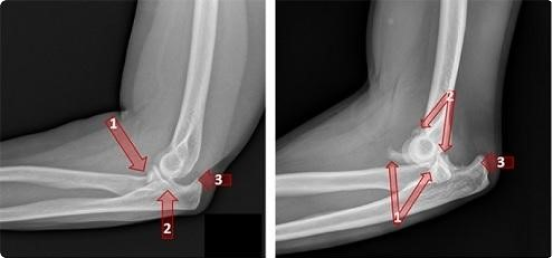

Figure: Xrays of elbow fracture dislocations. #1 shows the break in the radius. #2 shows the break in the ulna. #3 shows the elbow joint completely out of place, or dislocated.

Fractures and dislocations are common injuries that occur when there is a break or displacement in the bones of the elbow. Fractures can range from simple cracks in the bone to more severe breaks that require surgical intervention. Dislocations occur when the elbow bones are out of place, which can cause pain, swelling, and difficulty moving the arm.

Treatment for fractures and dislocations may involve using a splint or cast to immobilise the joint, as well as physical therapy to help restore movement and strength to the arm. In more severe cases, surgery may be necessary to realign the bones or fix the fracture.